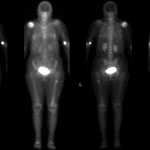

- Left total knee arthroplasty without osteolysis or other complicating feature

- Multiple mineralized densities posterior to the knee with the largest measuring 7 x 6 mm

- Geographic sclerosis in the distal femoral diaphysis

Left total knee arthroplasty without osteolysis or other complicating feature.

Multiple mineralized densities posterior to the knee with the largest measuring 7 x 6 mm, likely within a Baker’s cyst.

Geographic sclerosis in the distal femoral diaphysis, which likely represents a prior bone infarct.